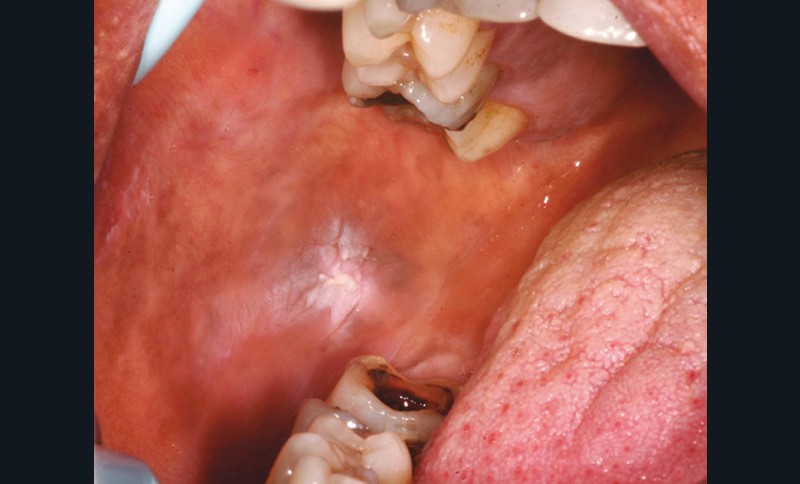

Les causes mécaniques sont les plus fréquentes. Il peut s’agir d’une dent fracturée (fig. 2) ou cariée, d’une prothèse mal adaptée, usée, d’un appareil d’orthodontie traumatique, ou de mastication sur les crêtes édentées (fig. 3).